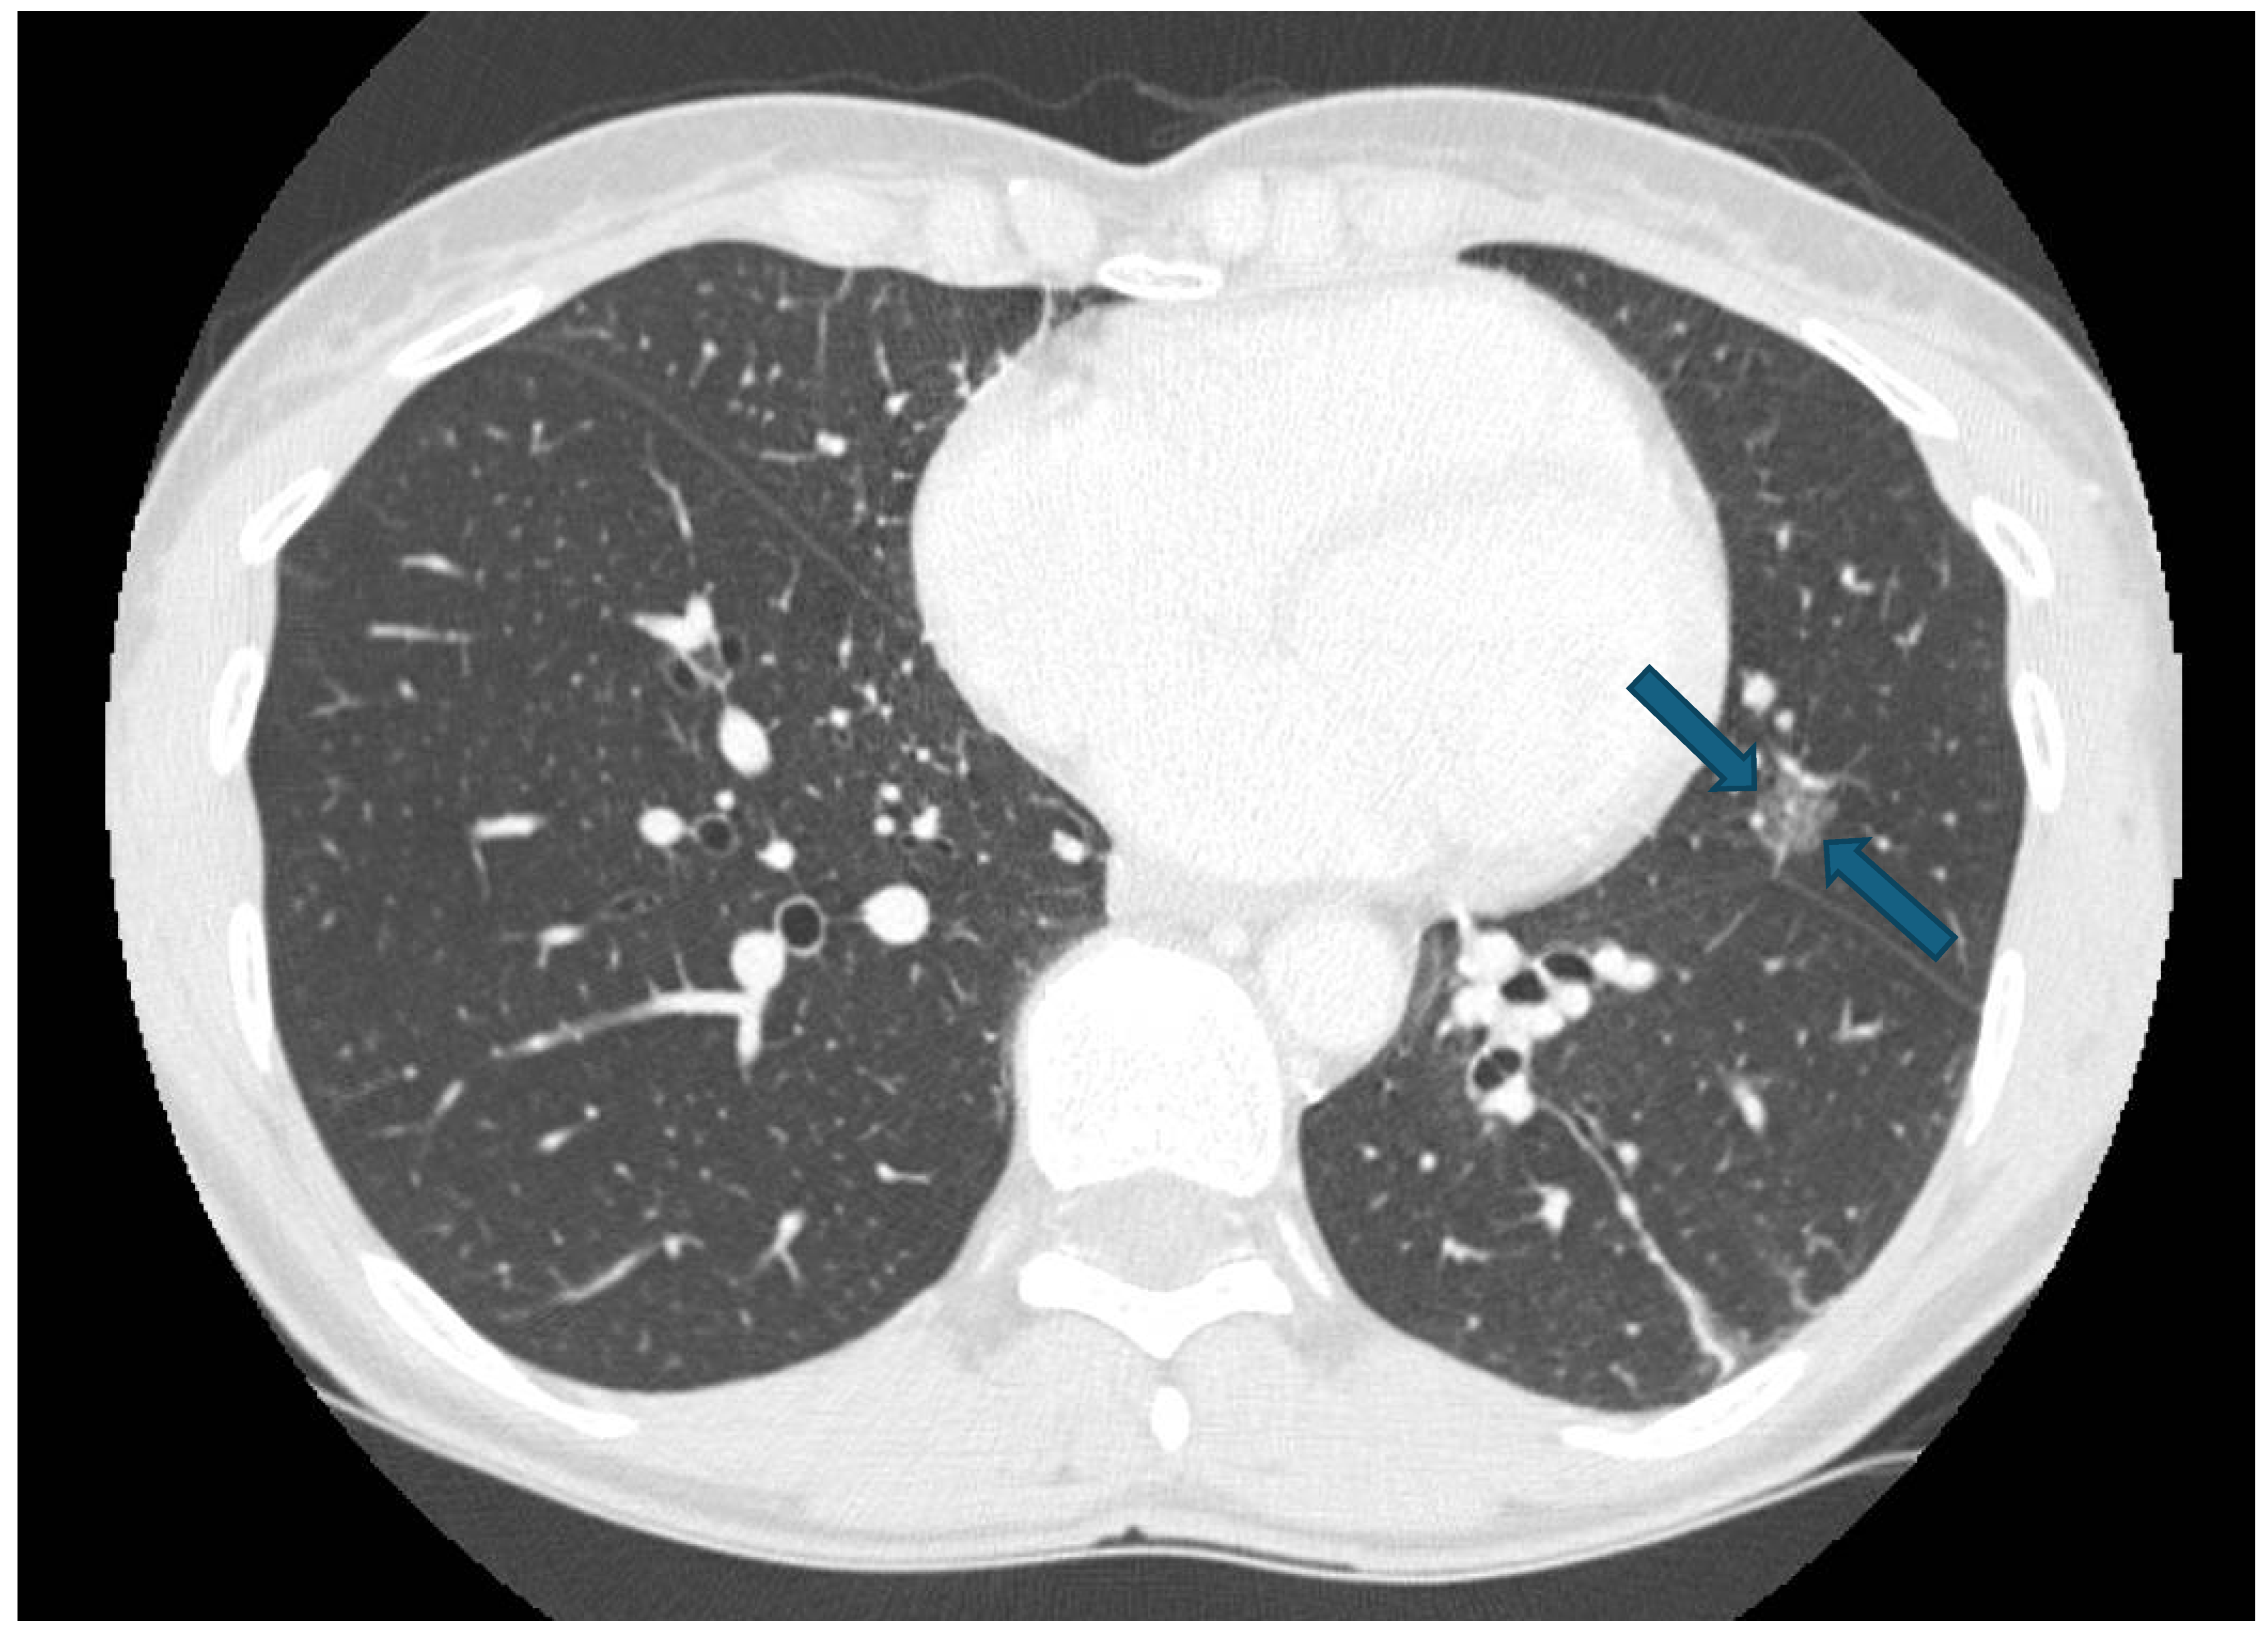

The patient came in 2024 to our attention for oncological assessment after the detection of a subtle enlargement of a subsolid nodule of 11 mm within the lower lingular segment on a recent chest CT scan, suspicious for primary lung disease or metastatic involvement (Figure 1). Pulmonary function testing demonstrated a preserved spirometry profile with notable findings of increased residual volume (RV) and RV/total lung capacity (TLC) ratio, indicative of potential air trapping. The case was discussed in a multi-disciplinary meeting and 3D reconstruction was performed and evaluated together with radiologists with expertise in lung cancer. Due to considerations about the nodule location, size, and reduced pulmonary function, segmentectomy was indicated to preserve lung parenchyma while ensuring appropriate oncological intervention.

Figure 1.

Preoperative CT scan.